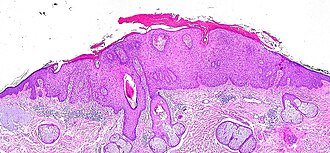

Microscopic

Features:[5]

- Epidermal nuclear atypia:

- Variation is size, shape and staining - must involve basilar layer.

- Nuclear enlargement - key feature.

- Hyperchromasia.

- Abnormal epidermal architecture:

- Palisading.[citation needed]

- +/-Parakeratosis - may alternate with orthokeratosis, esp. early lesions.[6]

- +/-Irregular acanthosis.

The sections show skin with basilar epidermal nuclear enlargement and hyperchromasia with irregular nuclear palisading. Hyperkeratosis and parakeratosis is present. A granular layer is present. The dermal-epidermal interface is sharply-demarcated. There is focal inflammation at the interface. Extensive solar elastosis is present.